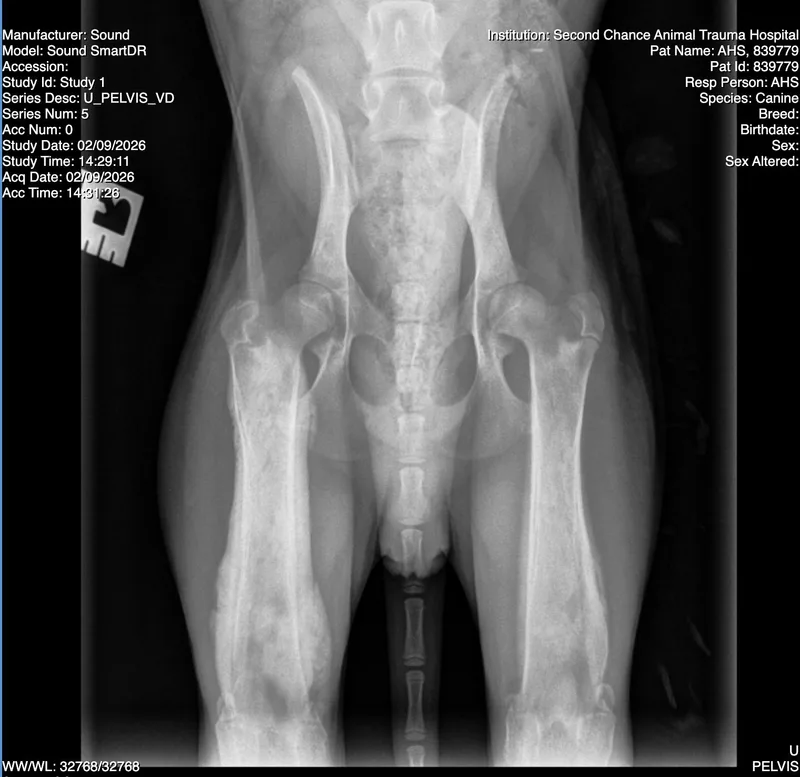

Jetty originally came to AZ Humane as part of a hoarding case with fur so matted that it was shaved. He also had the craziest leg x-rays that ended up being diagnosed as panosteitis - the equivalent of growing pains. He was hurting so bad because he somehow got the worst case of this our vets had ever seen! Jetty is now well-managed on NSAIDs and it is amazing what a difference they have made. This painful sad puppy has turned into a joyful, playful, happy-go-lucky guy who just loves life! He will need to be on the NSAIDs for a while, but thankfully carprofen is very affordable. He should outgrow this condition when he reaches full maturity - usually by 1.5-2yrs old it's a thing of the past. He has no longterm health concerns, and we even did repeat bloodwork to confirm his initial anemia was gone (it is). He's so healthy! It's been a few months since he joined us now. His fur is now growing in and we're getting to see how handsome this sweet boy will be when he's full grown. He's still pretty petit at 7-8mos (he was only 16lbs when we got him), so we think he will stay on the smaller side when full grown. Jetty loves snuggles once he gets to know you, and does great with other dogs large and small. We have not cat tested him, but there's a good chance he would do ok with them too. He hasn't been around kids with us yet, but again it's hard to see him having issues! Adopt: https://azhuskyrescue.com/adoption-application/